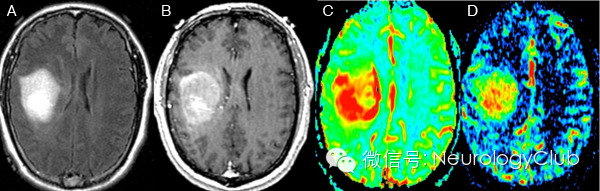

CT显示肿瘤呈边界不清的混杂密度影,常见瘤内出血所致高密度或囊性变、坏死;肿瘤跨胼胝体生长至对侧大脑半球时,呈“蝴蝶征”,水肿和占位效应明显。MRI在一定程度上能够揭示肿瘤的病理改变:T1WI呈不均匀低信号(图 1a),多合并坏死、囊性变或出血性改变;T2WI呈混杂高信号,中心坏死区为高信号,肿瘤生长区周围呈等信号,部分病变与肿瘤周围水肿分界不清,肿瘤内异常血管增生形成线样“流空效应”区(图 1b)。增强扫描肿瘤边缘呈显著对比强化,呈“花环”(ring/rim-enhancing)样(图 1c)、不规则环形、岛形或螺旋形改变;囊变性和坏死区周围肿瘤实质呈特征性“假栅栏征”,即圆形、椭圆形未强化区散在分布在强化区内,类似乳突蜂窝小房。DWI多呈高信号,ADC值明显减低。MRS提示NAA峰降低,Cho升高明显,MI峰较低级别星形细胞瘤低。灌注成像显示,病灶周围和病灶内有多处高灌注区(图 1d),提示大量肿瘤血管生成。胶质母细胞瘤虽具典型影像学特征,但仍需注意与颅内单发转移瘤、间变性胶质瘤、淋巴瘤等肿瘤性病变,以及脑脓肿、结核瘤、脱髓鞘假瘤等非肿瘤性占位性病变相鉴别。

(图2:胶质母细胞瘤)